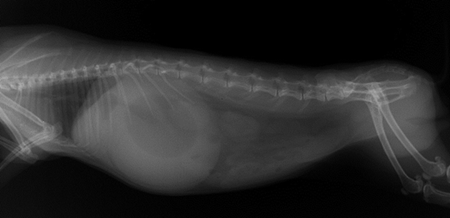

Radio 1 : Radiographie d’un iléus

Radio 2 : Radiographie d’une obstruction